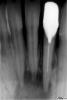

Rania Опубликовано 26 января, 2010 Поделиться Опубликовано 26 января, 2010 41 и 42 зубы живые, несмотря на кисту. Как такое может быть? Ссылка на комментарий

IgorD Опубликовано 26 января, 2010 Поделиться Опубликовано 26 января, 2010 41 и 42 зубы живые, несмотря на кисту. Как такое может быть? киста может быть расположена так, что зубы в нее не вовлечены, сосудисто нервные пучки в частности... А на Rо накладывается будто зубы в кисте... KT поможет определить локализацию кисты... Ссылка на комментарий

cactus Опубликовано 28 января, 2010 Поделиться Опубликовано 28 января, 2010 41 и 42 зубы живые, несмотря на кисту. Как такое может быть? у вас ведь не злокачественная опухоль, которая прорастает и разрушает ткани. Я даже сомневаюсь что то что у вас на снимке можно назвать киста. Ссылка на комментарий

Vareнька Опубликовано 28 января, 2010 Поделиться Опубликовано 28 января, 2010 41 и 42 зубы живые, несмотря на кисту. Как такое может быть? А кто пациент? Случайно не дама в районе сорока лет? Бывает у них такое как раз в области нижних резцов - периапикальная цементная дисплазия называтся Ссылка на комментарий

cactus Опубликовано 28 января, 2010 Поделиться Опубликовано 28 января, 2010 А кто пациент? Случайно не дама в районе сорока лет? Бывает у них такое как раз в области нижних резцов - периапикальная цементная дисплазия называтся и еще желательно чтобы дама была темнокожая, у белокожих реже Ссылка на комментарий

Whitebone Опубликовано 28 января, 2010 Поделиться Опубликовано 28 января, 2010 Надо бы с 31-м разобраться еще. В дополнение к проблеме с основным каналом вероятно наличие латеральных каналов. Сочетанная эндо- и периодонтопатология. Ссылка на комментарий